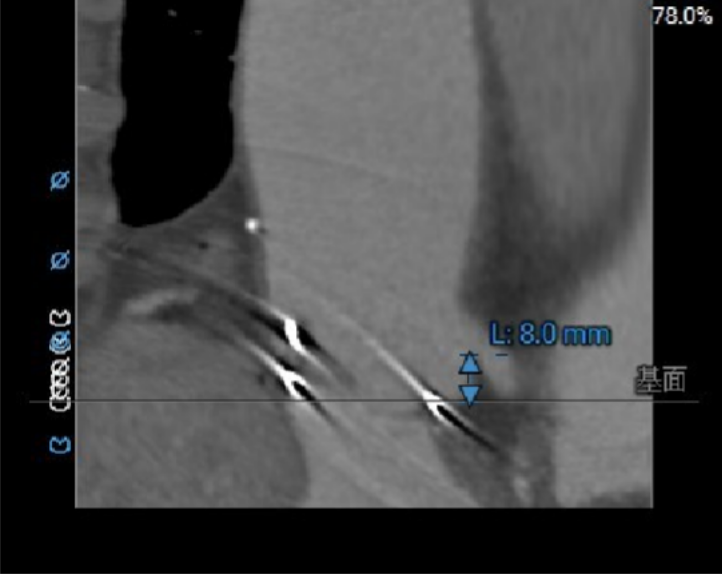

冠脉风险:LCA:8.0mm,RCA:11.4mm;外科瓣术后,SOV:34.0*36.3*36.4mm,STJ:33.8mm,冠脉堵塞风险低;